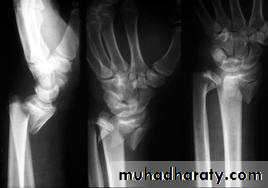

COMMINUTED INTRA-ARTICULARFRACTURES IN YOUNG ADULTS

In the young adult, a comminuted intra-articular fractureis a high energy injury. A poor outcome will result unless intra-articular congruity, fracture alignment and length are restored and movements started as soon as possible. For these patients a much higher standard must be set than would be accepted for the typical osteoporotic fracture. In addition to the usual posteroanterior and lateral x-rays, oblique views and often CT scans are useful to show the fragment alignment. The simplest option is a manipulation and cast. If the anatomy is not restored, then an open reduction may be necessary. The medial complex must be anatomically reduced, which may require open reduction through dorsal and palmar approaches and a combination of wires, plates, screws and bone grafts.